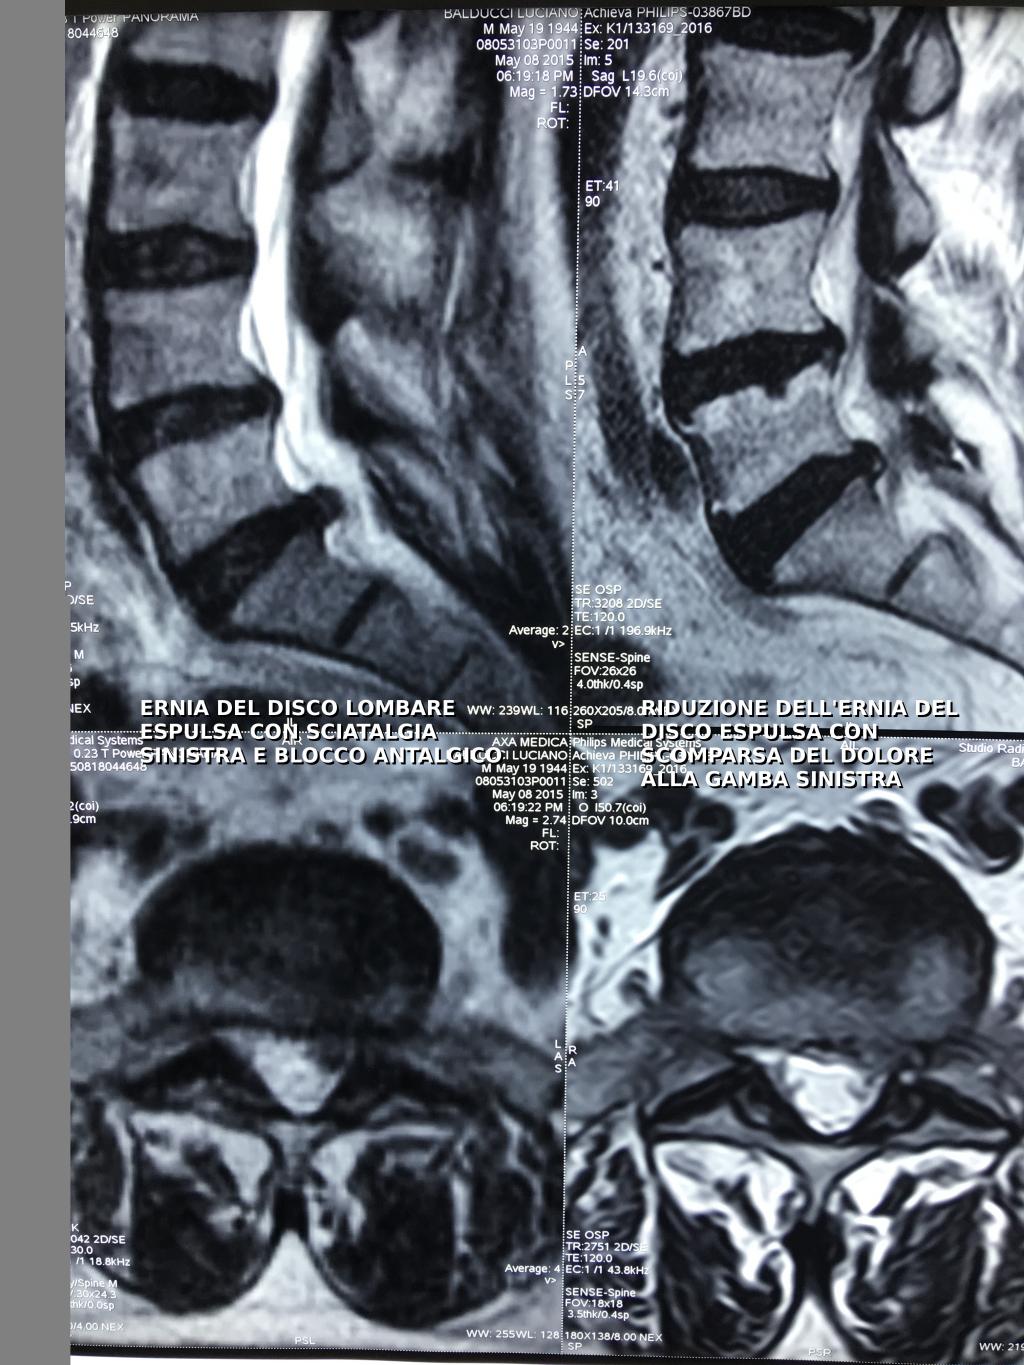

In questa immagine: Ernia disco lombare L5-S1 sinistra trattata con ossigeno ozonoterapia

Risonanza di controllo Ottobre 2017